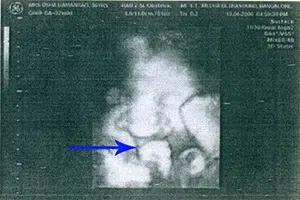

Detection and Diagnosis: In most cases, cleft lip and cleft palate are identifiable at birth, often without the need for special tests. Increasingly, these anomalies are visible through prenatal ultrasounds, which use sound waves to create images of the developing fetus.

Cleft lip can be detected via ultrasound as early as the 13th week of pregnancy, with increasing accuracy as the pregnancy progresses. Cleft palate, when isolated, is more challenging to detect via ultrasound. When not identified prenatally, a physical examination of the mouth, nose, and palate is the standard approach for post-birth diagnosis. In certain situations, amniocentesis may be recommended to screen for other genetic conditions.